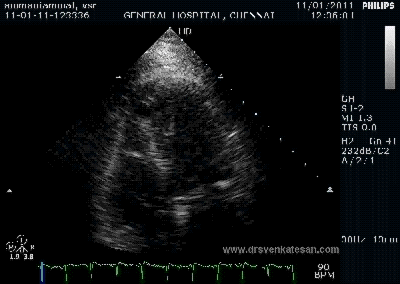

Here is 55 year old women came with extensive anterior MI with lower septal rupture.(She belonged to type 3 of the above scheme)

Note the septal rupture is visible even in 2D Echo